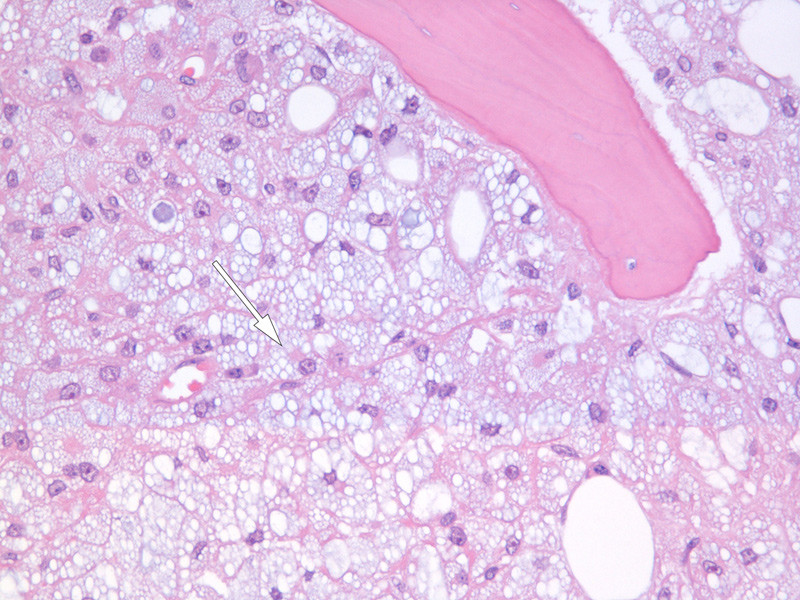

Ved primær vurdering av benmargsutstryket fant vi en cellefattig, fettrik marg der det var rikelig med vakuoliserte makrofager, såkalte skumceller (fig 1). Det var dysplastisk erytroid og myeloid rekke uten blastutvikling. Benmargsbiopsien ble beskrevet med massiv infiltrasjon av makrofager og hypoplastisk hematopoese (fig 2). Makrofagene inneholdt vakuoler av noe varierende størrelse.

Ved ny granskning av benmargsbiopsien farget man også dette materialet med PASM og kongorødt. Vi fant da inklusjoner i makrofagenes vakuoler, som ble farget henholdsvis svart og rødt.